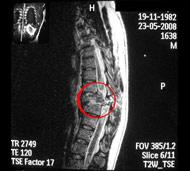

- Магнітно-резонансна томографія (МРТ). МРТ використовує магнітну силу і радіохвилі, щоб відтворити зображення, отримані через комп'ютер. Це допомагає в ситуаціях, коли необхідно розглянути спинний мозок і виявити грижу міжхребцевого диску, згустки крові і інші утворення, які можуть здавлювати спинний мозок. Але МРТ не можна проводити пацієнтам з серцевими водіями ритму або постраждалих, яким необхідна апаратура, що підтримує життєдіяльність організму чи пристосування для витягування шийного відділу хребта.